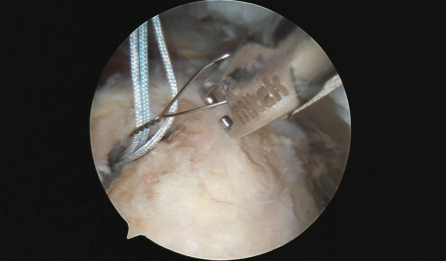

Medical HD Wireless Transmission

Technical Advancements:

1. Uncompressed, lag-free HD wireless image transmission

2. FCC-compliant electromagnetic radiation design and manufacturing

3. FDA-compliant wireless coexistence design and manufacturing

4. FDA 510K-compliant development and production of wireless HD endoscope

systems

5. 510K-compliant network security for firmware and system software development

6. Wireless encrypted control for system communication

Applications:

1. Wireless HD endoscopes in the medical industry

2. Portable forensic endoscopes for autopsy and crime scene investigation

3. Lightweight, self-powered wireless endoscopes for disaster relief and mobile

medical support

William John

Lead Inventor & Total Designer

Chief Technology Development Officer

EL3 Imaging

Developer of the Nuvis-2K Wireless HD Endoscopic Camera System

★ FDA 510(k) Cleared K242606 | November 20, 2025